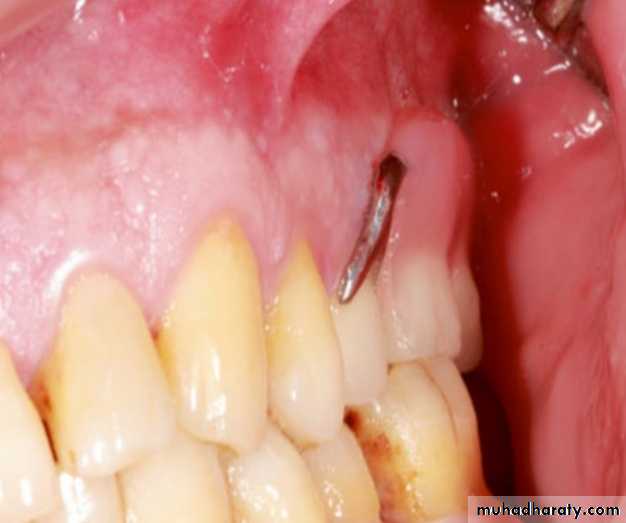

Food impaction happens usually when the acrylic denture base is not well adapted to the abutments .

The reason is usually starting the treatment without restoring the abutment teeth.

Therefore, restarting the treatment with proper planning including restoring the abutments rather than relining is more appropriate in these situations.

However, if the food trap is due to an insufficiently extended denture base, the solution may be a relining.

If a reduced salivary flow is present, medications increasing the flow rate may be pre-scribed or chewing gums and fluids stimulating the flow may be recommended to the patients. When the acrylic denture base of the RPD is

not well adapted to the abutment tooth, food impaction is unavoidable